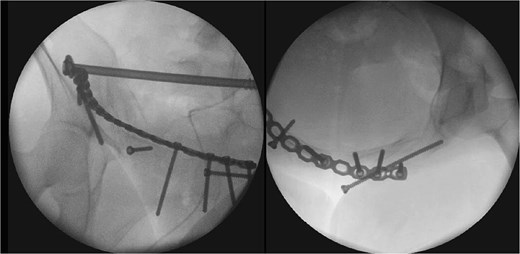

After one week of monitoring in the ICU, where she remained stable without need for ventilatory support, the patient was transferred to the ward. She then underwent the first surgical stage in supine position. Anterior pelvic fixation (Fig. 3a) was performed via a Pfannenstiel anterior approach combined with the first window of the right ilioinguinal approach, using a 3.5-mm reconstruction plate on the right anterior column crossing the pubic symphysis and a 3.5-mm retrograde screw in the left anterior column, inserted through the same Pfannenstiel access. During the same procedure, a 7.3-mm trans-sacral screw was placed in S1 on the right to stabilize the sacral fracture (Fig. 4). The surgery lasted ⁓3 h, and the patient was transferred to the semi-intensive care unit for postoperative monitoring.

The two-stage approach addressed initial severity (Fig. 3), using a Pfannenstiel and ilioinguinal approach for anterior fixation and an S1 trans-sacral screw for sacral stability [10, 11], followed by lumbopelvic fixation for posterior stability [12]. A 3-week delay, partly due to material unavailability, caused fibrosis, complicating reduction [13]. Seroma drainage in the second stage mitigated infection risks from the Pfannenstiel approach. ICU monitoring reflected management complexity despite stability [14]. Follow-ups over 18 months demonstrated functional recovery, quality-of-life gains, and psychological stability by 6 months, sustained to 18 months (Table 2, Fig. 7), despite early anxiety; this contrasts with studies linking severe psychological distress to poorer outcomes in Tile C fractures, suggesting early intervention mitigated these risks [5]. The Majeed score’s specificity, despite lacking a Portuguese version, and SF-12 supported outcomes analysis [15]. Pain assessment via the Numeric Pain Scale (NPS) revealed persistent lumbar pain radiating to right lower limb until the 4th week (NPS 4), resolving significantly by 3 months (NPS 1) and absent thereafter (Table 2, Fig. 7), consistent with rehabilitation progress and lumbopelvic fixation stability. This case underscores surgical timing challenges, the impact of delayed fixation, and multidisciplinary care’s value.